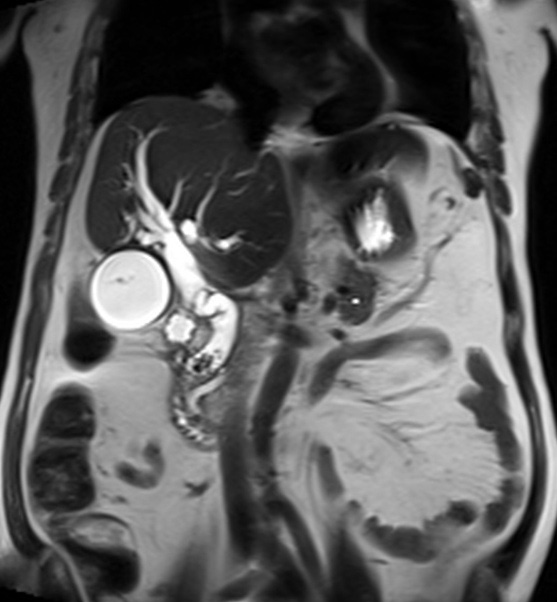

| |

Meme cas en coupe

IRM coronal ponderee sur T2

. Images du calcul ( hyposignal ) est en vue tres

net a la portion inferieure du canal

choledoque |

Images de

recontructional en 2D de voie biliaire intrahepatique et

extrahepatique normale . La vesicule biliaire est en

vue tres net . Duodenum D2 et D3 etre en vue .

Cholagio-IRM sequence ponderee en T2 ( Thick Slab ) |